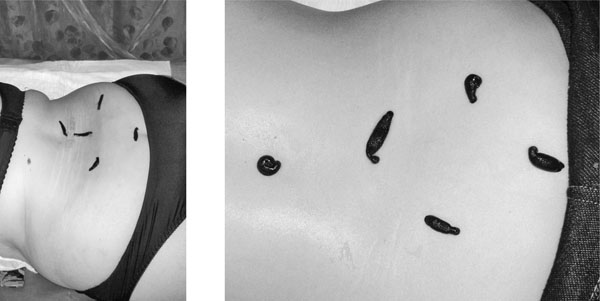

Если в пупочке пиявочка отвалилась самостоятельно менее чем через час – следующую постановку, на низ живота, можно ставить без пупка. Три штуки над лобковой костью, если девушка средней комплекции или худенькая. Если на третьей постановке (только в пупок) – пиявка осталась маленькая и печень явно еще не «включилась» в работу – низ живота (3 шт.) совмещаем с постановкой в пупок – 1 шт. Постановки – раз в 4–7 дней.

Постановка пиявок – малый таз

Четвертая постановка – малый таз и продолжение работы с печенью (если постановкой ранее пиявка осталась маленькой). 1 шт. в пупок, от 3–5 шт. на низ живота (в зависимости от комплекции пациента – 100 кг и более – можно 5 шт.). Говорить о важности кровообращения в области гинекологии и урологии не нужно – на долю этих зон приходится половина всех диагнозов. Данные направления будут рассмотрены отдельно. В малом тазу у мужчин – придатки и предстательная железа, а у женщин – матка и яичники. Но даже если проблема связана, например, с суставами, игнорировать эту зону нельзя – слишком большое участие принимает она в общем круге кровообращения, и значимость нормальной работы таких важных гормональных органов несомненна при снятии любых диагнозов, в том числе артритов и артрозов. В пупочек ставим так же, обрезанным шприцем, а в низ живота (надлобковая зона) можно поставить вакуумной баночкой. Такие баночки продаются в аптеке по две штуки в упаковке – они полностью мягкие, без пластмассовой ножки. Сажаем в банку 2–3 шт., чуть сжимаем банку для эффекта присасывания и ставим на нужный участок. Как одна пиявочка начнет есть – убираем банку с остальными. В банке у пиявки есть зона выбора – она сама встанет куда нужно. Пупок фиксируем ватным диском и кусочком липкого бинта, а низ живота – прокладкой и эластичным бинтом.